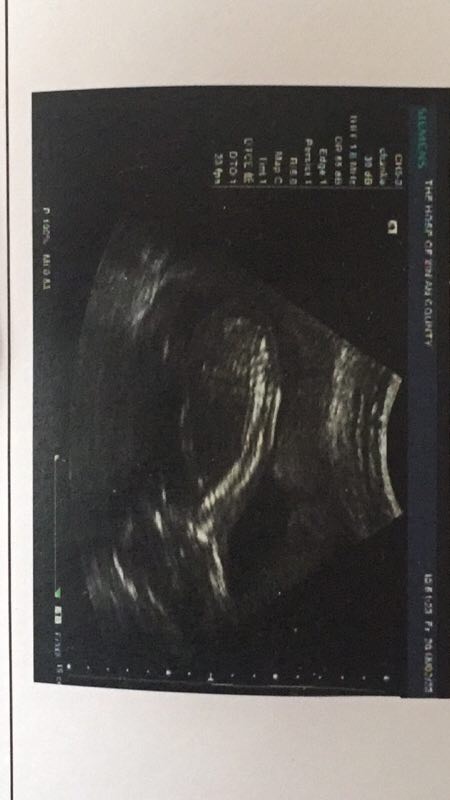

孕20周+0天

A军[帖主]:发育正常

挺好的

A军[帖主]:能看出来男孩女孩吗